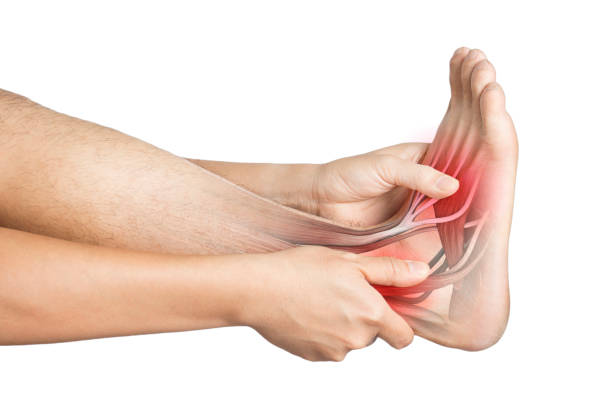

통풍은 대개 발적을 침범하며, 발적 주위의 관절에서도 통증을 일으킬 수 있습니다. 대개 발목, 무릎, 발가락 등을 포함하며, 통증은 심할 때 걷는 것이 거의 불가능할 정도로 심해질 수 있습니다.